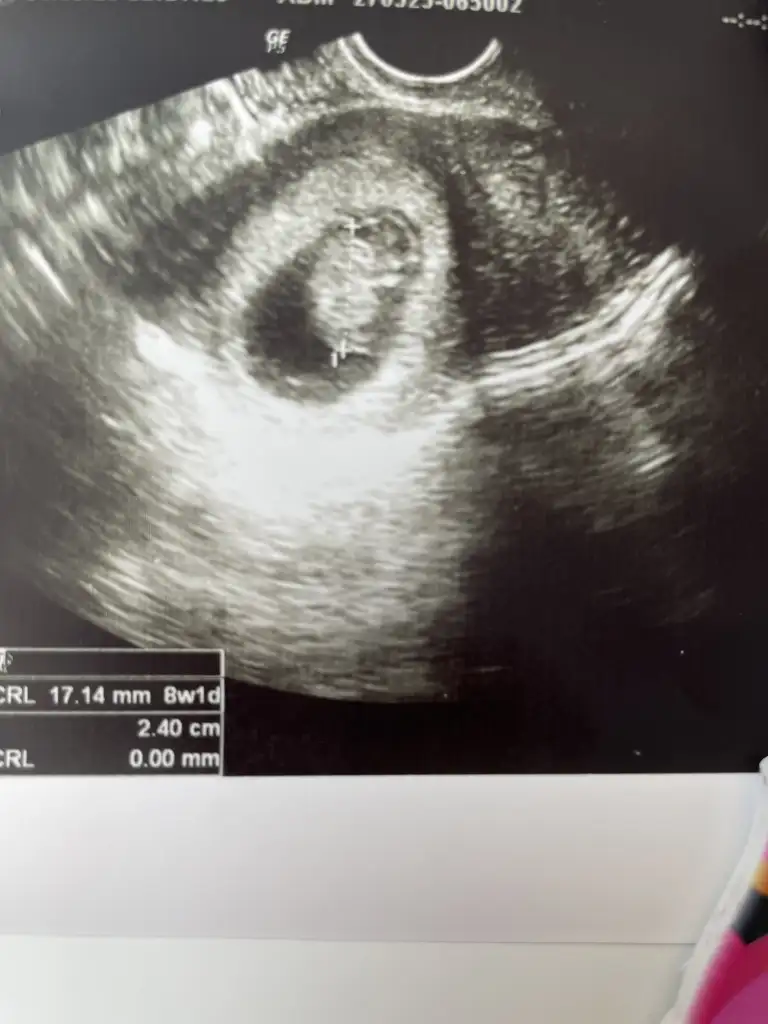

Ayyyy minnacık yaa fasülye

Kız hissettim bilmiyorum amaaaqqKızlar cinsiyet tahmini yapacak var mı çok erken amaD Dua ile soguknevalee ebraarrr E esrarengizl N nryyy Susluprenses2473

Kız diye içimden geçti ams kese şekline bakarsak erkek görünüyorUltrason fotoğrafı var atayım mı ki